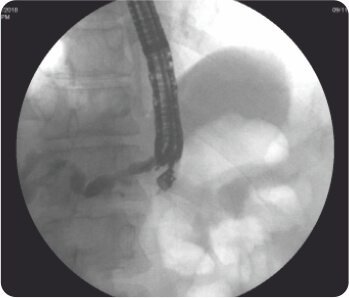

EUS guided puncture of IHBRD in the second segment of liver was done from stomach and after the cholangiogram, the tract was dilated sequentially using cystotomes till 10F and a 60×10 mm fully covered biliary metal stent was deployed connecting the stomach and the second segment of liver. A 7F 7cm double pigtail plastic stent was deployed within the metal stent to prevent its displacement. There were no periprocedural complications and the patient underwent chemotherapy after normalization of bilirubin. During follow-up 3 months after the procedure, the patient’s LFT remained normal.

Cholangiogram